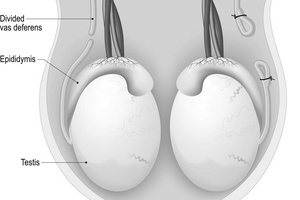

Вазэктомия – это метод хирургической контрацепции, заключающийся в перевязке семявыносящих протоков.

Операция стерилизации мужчины намного проще и безопаснее, чем перевязка маточных труб у женщины. Суть вазэктомии заключается в следующем. Сначала на коже в низу живота делается короткий надрез. Затем из семявыносящих протоков иссекается небольшой сегмент, после чего они зашиваются. Однако образовавшаяся преграда не позволяет сперматозоидам проникать в семенную жидкость. Операция, выполняемая обычным способом, продолжается около 15 минут. В последнее время широко распространилась китайская методика, при которой процедура длится в течение 8 минут. Причем данный способ исключает надрезы и наложение швов.